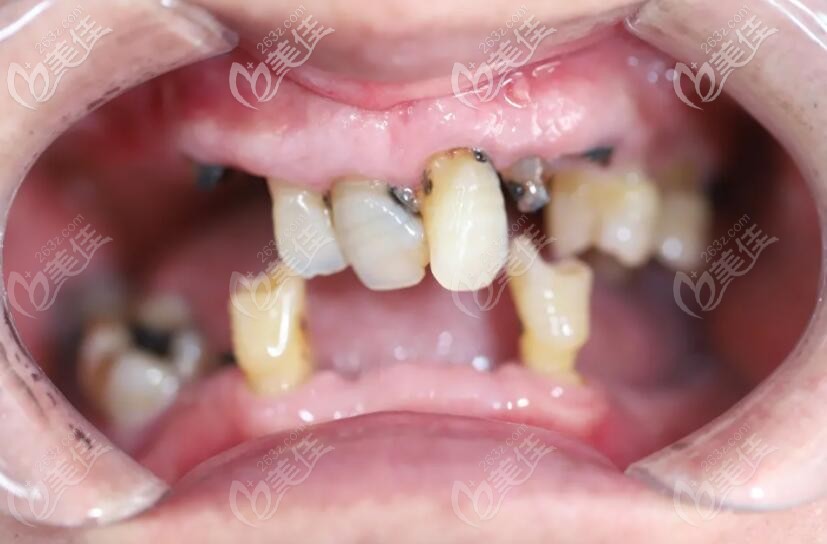

重度牙周炎种牙图片,重度牙周炎图片

重度牙周炎图片

重度牙周炎

严重牙周病图片